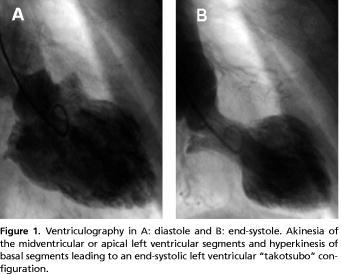

Takotsubo cardiomyopathy is today categorized as a primary cardiomyopathy [9]. The syndrome is predominately observed in postmenopausal women, and is typically triggered by preceding emotional or physical stress. The syndrome was first described in Japan and named takotsubo-like LV dysfunction in reference to the associated end-systolic left ventricular morphology resembling a fishing pot (tako tsubo) with a narrow neck and a round bottom used for trapping octopuses in Japan [1] ( Figure 1 ). Patients suffering from TC may in the acute phase have electrocardiographic changes very similar to those in the event of STEMI, whereas the changes later on are only sparsely described [10-12]. With focus on the electrocardiographic characteristics we will present our first experience with TC, and discuss possible pathophysiological mechanisms.

Four patients with a suspected acute myocardial infarction had coronary angiography performed ≤ 12 hours after symptom onset. The remaining three patients underwent coronary angiography within 24 hours, three and 11 days after the onset, respectively. No obstructive coronary disease was identified in any of the patients. The delay in the first case was due to an attempt of haemodynamic stabilizing the patient with inotropic agents at the local hospital. In the second case the patient was initially hospitalized for surgery because of a fracture of the hip, and subsequently transferred for coronary angiography because of ECG changes. An 81 year-old woman was admitted with pneumonia, and due to continued chest pain a coronary angiography was performed on the eleventh day. Three patients had normal coronary arteries, three had mild luminal irregularities and one had a non-significant stenosis distally in the ramus descendens anterior. Ventriculography was performed in four patients (Figure 1).